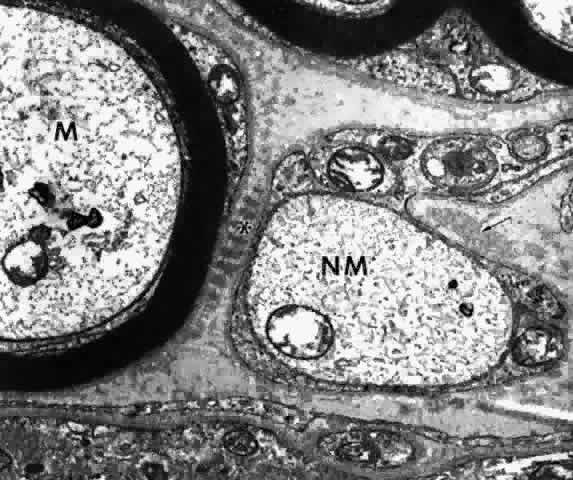

The ciliary body is well supplied with nerves, both myelinated and unmyelinated (Fig. 46), of parasympathic, sympathetic, and sensory types. The parasympathetic nerve fibers originate in the Edinger-Westphal nucleus and travel in the oculomotor nerve.51,77 They synapse in the ciliary ganglion and in small numbers of local ganglia within the ciliary nerves, before forming extensive plexuses around the ciliary muscle fibers. Accommodative function is subserved by this parasympathetic system. Some have questioned whether synapse is actually made in the ciliary ganglion.78 Most studies, however, support such synapses as the major function of the ciliary ganglion.51,79

Fig. 46. Myelinated (M) and unmyelinated (NM) nerves surrounded by Schwann cell cytoplasm. Ciliary muscle fiber below. Long-spacing collagen fiber (asterisk) is a degenerative change in this 20-year-old patient. Small elastic fiber (elaunin) in bend of Schwann cell (arrow). (X 33,300)